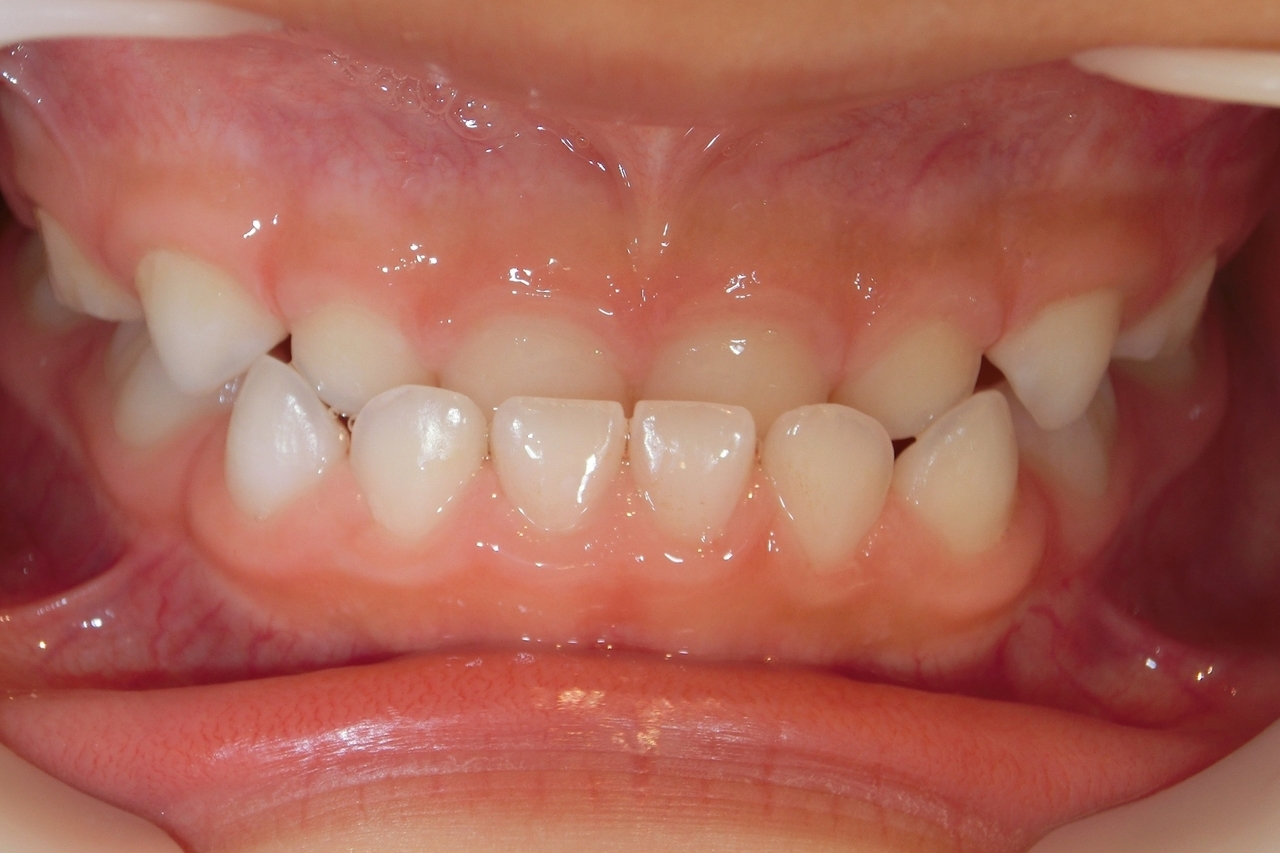

治療後

治療の副作用(リスク)歯の動き方には個人差があり、予想された治療期間が延長する可能性があります。。床矯正の使用状況、矯正歯科治療には患者さんの協力が必要であり、それらが治療結果や治療期間に影響します2次矯正が必要になる場合もあります。